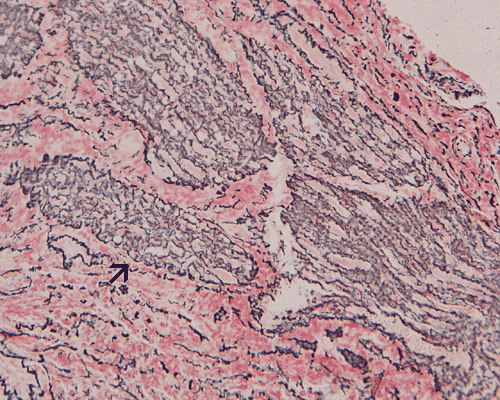

The surgery removed several irregular fragments of tan, soft tissue for examination that were 2.5 x 1.2 x 1.0 cm in toto. Histologically, the lesion is a highly cellular neoplasm with tumor cells packed in solid sheets and without a specific architectural pattern (Panel D). Small, focal necrosis is also present (not shown). The tumor has rich vascularity and the endothelial cells seem to be active (Panel E). Almost all the tumor cells have only a thin rim of amphophilic cytoplasm, large nuclei with prominent nucleoli (Panel E and F). Clear cytoplasm is present in some tumor cells. In general, the cells do not look epithelioid or spindle. In some of the tissue fragment, the tumor shows invasion into the peripheral nerve root with dissection of the nerve fibers (Ú in Panel G and H). This phenomenon is well demonstrated by reticulin stain (Panel I) and immunohistochemistry for neurofilament proteins (Panel J). About half of the tumor cells are strongly positive for vimentin (Panel K). There is also scant positive tumor cells for S100 protein (Panel L) and cytokeratin AE1/3 (Panel M). The tumor cells are negative for neuorfilament proteins (Panel K) and smooth muscle protein (Panel N).

A variety of histologic pattern may be encountered and thorough sampling is strongly recommended. Microscopically MPNSTs are highly cellular tumor featured by spindle cell proliferation and a high degree of variation, resulting in what is referred to as a “tapestry” appearance. While some tumors show only minor pleomorphism, a moderate to high level of nuclear pleomorphismare often present. Pallisading arrangement of tumor cells as that can be demonstrated in schwannoma is uncommon. Alternating areas of high cellularity and low cellularity can also be encountered. Epithelioid MPNST refer to a group of MPNST that are composed predominantly of epithelioid cells. These tumors tend to arise more often in superficial soft tissue.

The tumor under discussion is undifferentiated or poorly differentiated. The scant positive cells for S100 protein cannot strongly support a schwann cell origin. The lack of expression of EMA does not support a peirneurial or meningothelial origin. Therefore, these results do not suppoart a diagnosis of malignant peripheral nerve sheath tumor (MPNST) or meningioma. Both entities are unusual in this age group. While many MPNST may express cytokeratin AE1/AE3, the expression of a scant amount of cytokeratin does not totally rule out the possibility of a MPNST. Although the peripheral nerve bundles are diffusely infiltrated by the tumor as shown in Panel G and H and may suggest a malignant tumor arising from a nerve trunk, there is a lack of solid evidence to prove that this tumor is arising from a nerve trunk. Although a MPNST is suspected, the age and location is quite usual for this entity. The tumor under discussion is best classified as an undifferentiated sarcoma.